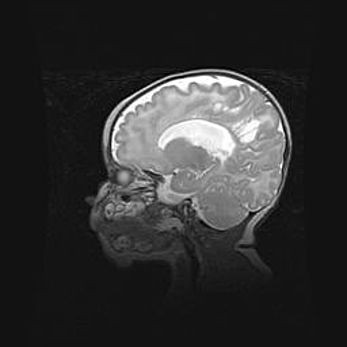

Аномалия Денди-Уокера. Признаки гипоплазии мозолистого тела.

Возраст: 5 месяцев 3 дня

Вес: 5550 г

Пол: мужской

Окружность головы: 39 см

Срок гестации: 40 недель

Аномалия Денди-Уокера – это порок развития головного мозга, для которого характерна триада симптомов: гипотрофия или аплазия червя мозжечка и/или полушарий мозжечка, расширение четвёртого желудочка с формированием ликворной кисты задней черепной ямки, гипертензионная гидроцефалия различной степени.

Гипоплазия мозолистого тела относится к дефектам внутриутробного этапа развития мозговой ткани, возникающим в процессе закладки структур головного мозга, что происходит на начальных этапах развития эмбриона.